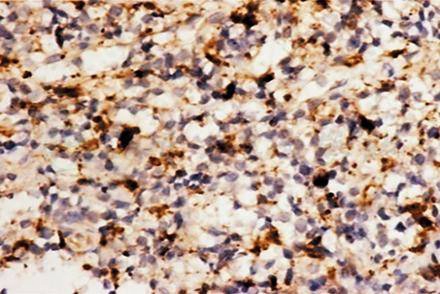

多发性骨髓瘤的瘤细胞分化程度有很大差异,瘤细胞可能异型性大,出现核分裂象(图1)。这些病理表现易与特发性淋巴增生性疾病、未分化肉瘤、弥散性大B细胞淋巴瘤和无色素黑色素瘤相混淆。

图1 组织病理检查见瘤细胞小,形态不规则,部分细胞质呈空泡状 HE×400